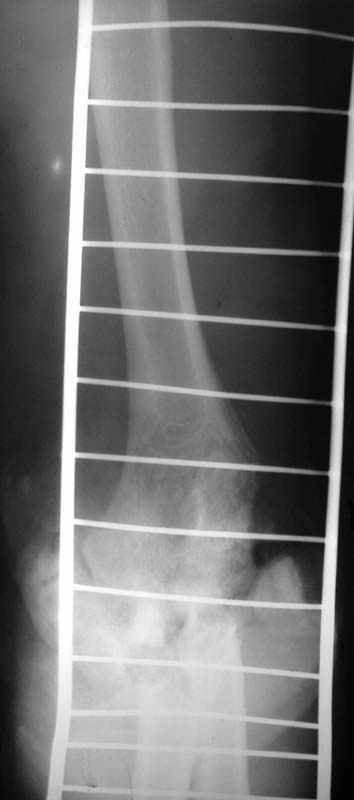

Уважаемые коллеги! Мужчина, 30 лет. В состоянии алкогольного опьянения заснул на рельсах и, по собственным словами, <слегка зацепился за трамвай>.

Обширная почти циркулярная (3/4 рана), в которую выстоят осколки костей с фрагментами суставной поверхности. Обширные ушибы и размозжения мягких тканей вокруг раны. Пульсация на лучевой артерии удовлетворительная, на локтевой слегка ослабленная. Снижение чувствительности в пальцах.Предложения по тактике лечения? Заранее благодарю!!! С уважением,А.В.ВладзимирскийДонецкий НИИ травматологии и ортопедииДонецк, Украина